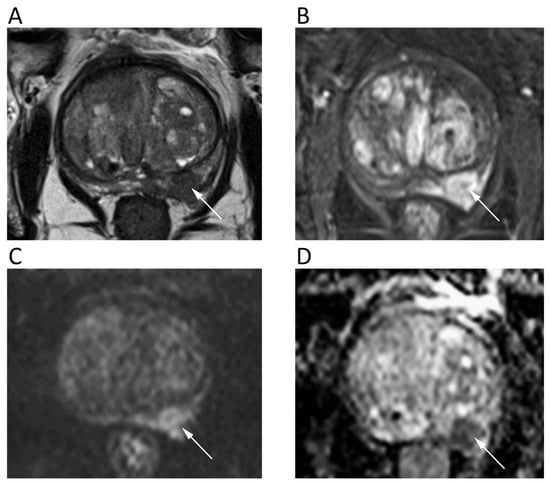

9. Gynecological

10. Urinary System and Adrenal

11. Prostate